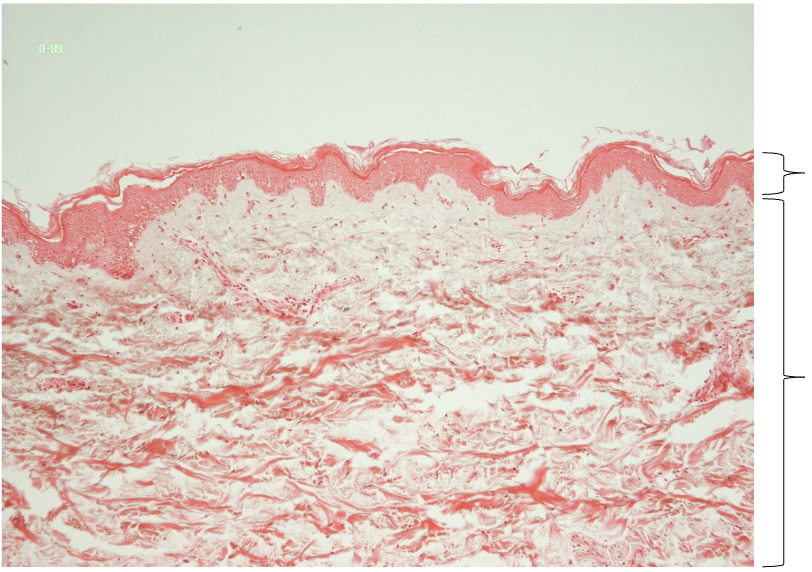

Label

Thin skin